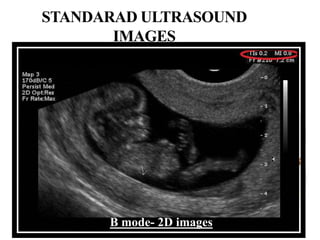

ULTRASOUNDIMAGESINCLINCALPRACTICE

 B-mode–two dimensional (2-D) images

STANDARAD ULTRASOUND

IMAGES

B mode- 2D images